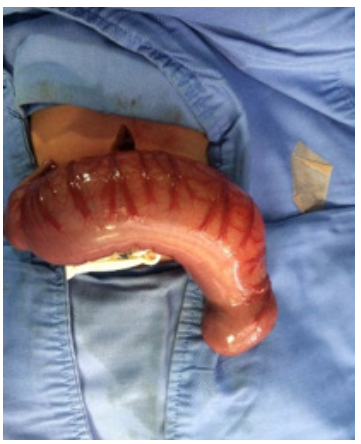

Invasive ventilation was initiated and a nasogastric tube was passed in-situ. An abdominal x-ray showed a large dilated loop of bowel (Figure 2), without a double bubble sign, ruling out duodenal atresia. Based on those findings, in her third day of life, an exploratory laparotomy was performed. A right colon atresia type III (Grosfeld classification) 11 was identified, with a difference of proximal distal caliber from 10 to 1 (Figure 3). A derivative Hartmann's colostomy was performed, given the difference of caliber size that did not allow primary anastomosis. Rectal biopsies were taken, reporting ganglion cells and ruling out Hirschsprung's disease.